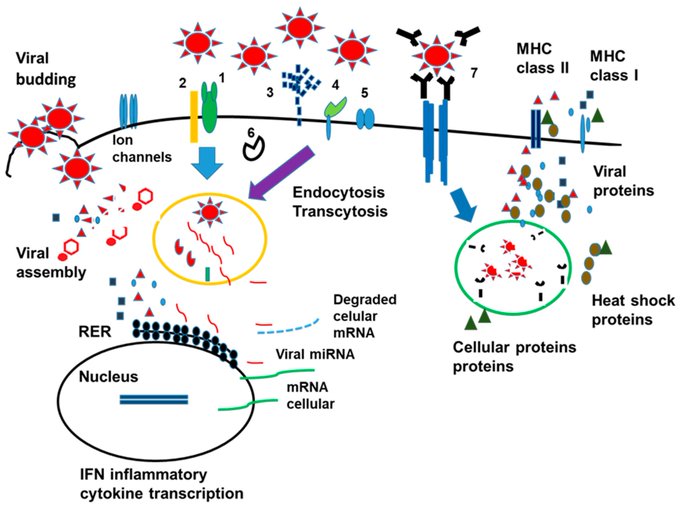

Autoimmunity and Immunodeficiency in Severe SARS-CoV-2 Infection and Prolonged COVID-19.